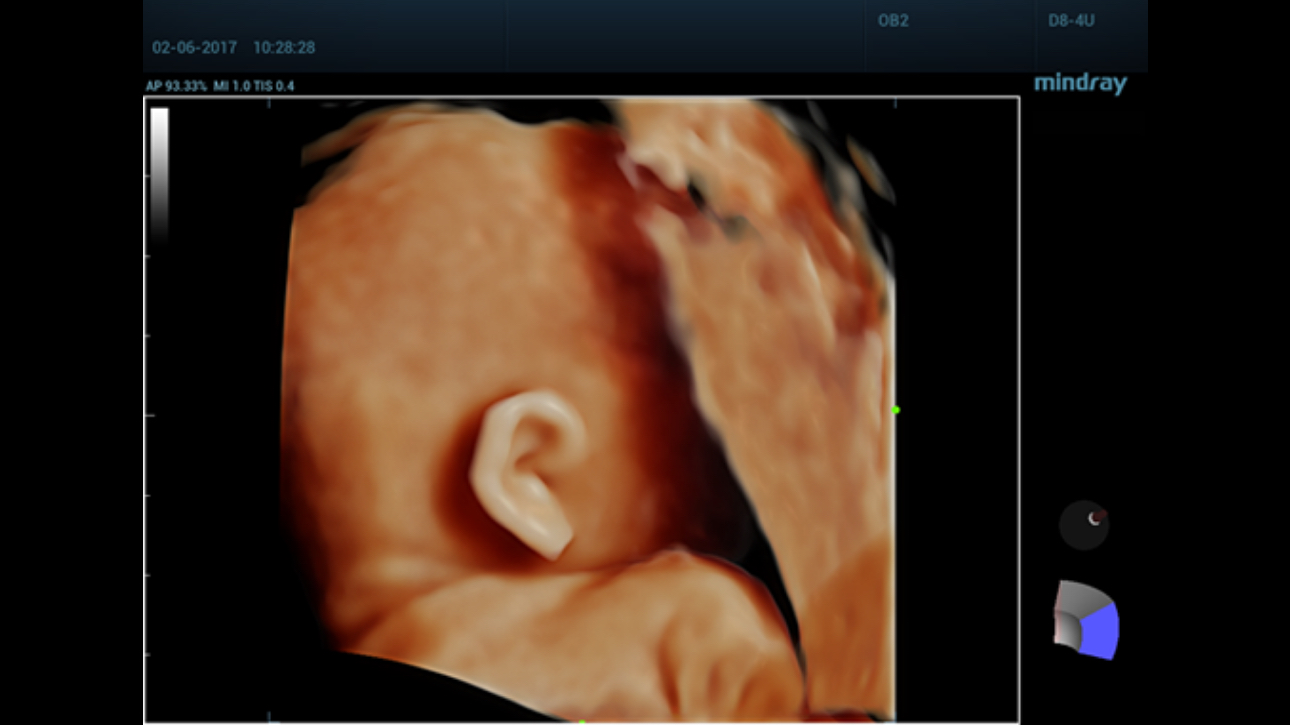

Comprehensive upgrading on iLive to significantly improve the detailed resolution as well as anatomical realism. Hyaline is a new rendering method that dynamically applies transparency to rendered structures for a more comprehensive view of anatomy, therefore better displaying internal anatomy from a solid surface.